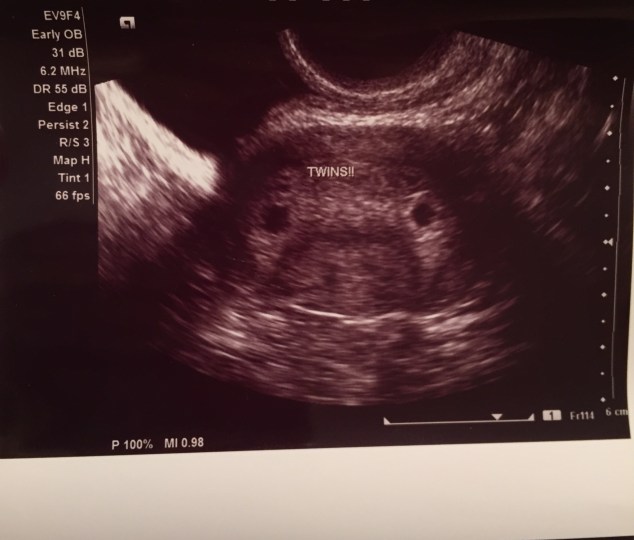

But the joy quickly turned to continued investigation to find out where the second embryo had implanted, if it had. After checking my tubes and ovaries, and seeing nothing, they went back to my utereus where …. Baby #2 was! Cue my messy tears at this moment! (I will forever be grateful for the kindness of the OB Intern who grabbed me Kleenex and squeezed my hand.) Baby B also looked great, showing a yolk sac and a fetal pole – both awesome signs of development, especially that early. They chalked the pain up to a growing uterus and possibly some pressure on my ovaries on my many cysts. But, I left that lab appointment that day with some BIG news – we were having TWINS!

October 20th – heartbeat appointment: The next day, my bleeding had nearly tapered off, which was a relief. Josh was incredibly optimistic going into our heartbeat appointment (in his words a “8 ½ out of 10” while I was about a 2.) As I laid on the table, I closed my eyes and waited. And within the next 5 seconds we heard her say she saw our two great looking babies with heartbeats! PRAISE THE LORD! We got to see the heartbeats waves this time, not quite yet hearing them, but seeing those precious waves were amazing.

Our measurements looked perfect and the babies hearts were both right at 112 bpm. We cried and sighed tears of relief. They then showed me the bleeding was caused from a subchorionic hemorrhage (SCH) located in my uterus, right between the two babies. While this only happens in about 1% of all pregnancies, it is more common in IVF pregnancies, occurring in about 50% of cases. Our doctor and team felt hopeful that with bed rest and care, this SCH could heal itself without causing harm to the babies. We simply need it to get smaller, not bigger. There is a slight increased chance of miscarriage with an SCH (3-4%). The risk comes that if it grows, it can cause the placenta to pull away from the uterine wall and bleed out everything in the uterus. Guess what? We are claiming victory that this will not be our story! So bed rest it is. Our doctor warned us that this gushing bleeding moment might happen again so to be prepared.

October 31st – ultrasound appointment: After another week of bed rest, we went back and saw our growing little babies! They were both the size of blueberries, measuring over a half inch, with heartbeats in the 150’s. They are starting to look more and more like babies already, and only at 7 ½ weeks! Our hearts are so full.